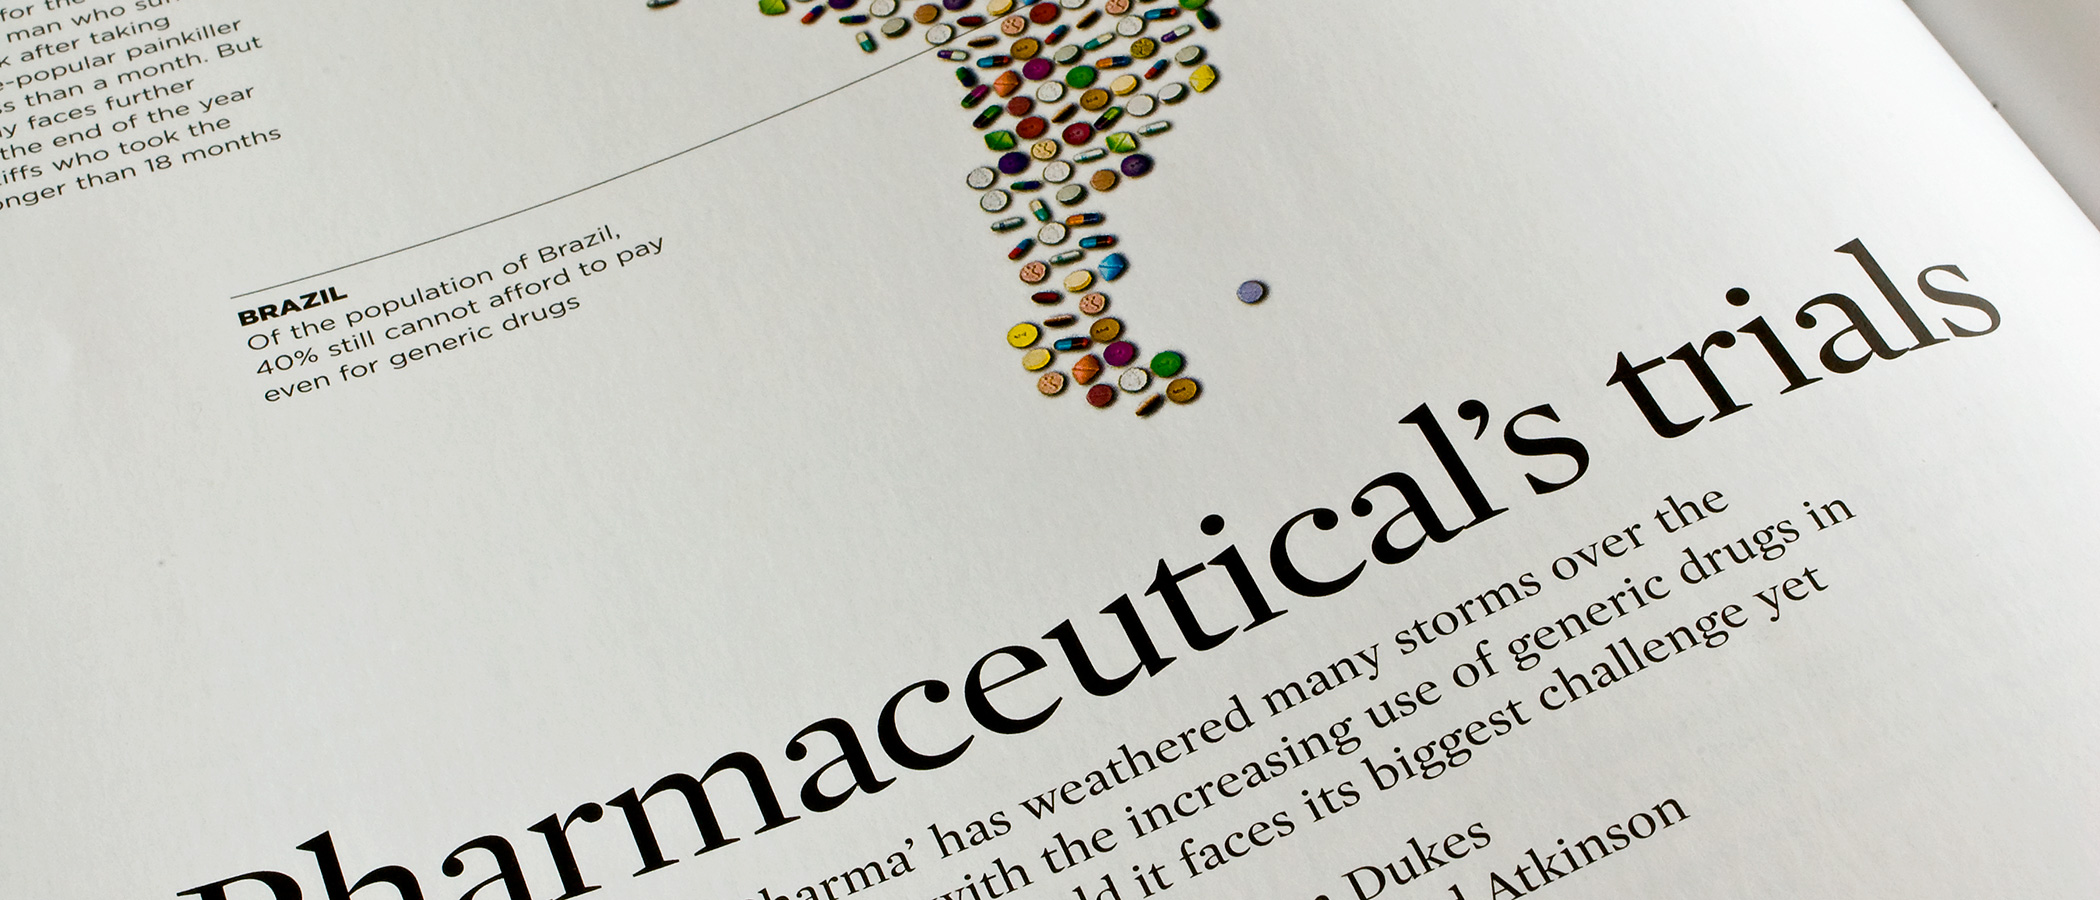

World Business is a monthly business magazine published by Haymarket. My work as design editor consisted in refining the overall design of the publication and defining the tone of the photography and illustrations, which are commissioned for different issues. The illustration on this page was my own, designed to accompany the article ‘Northern Stars’, focusing on the ‘cultural, institutional and economic conditions that make the Nordic countries the envy of the world’.

World Business Magazine